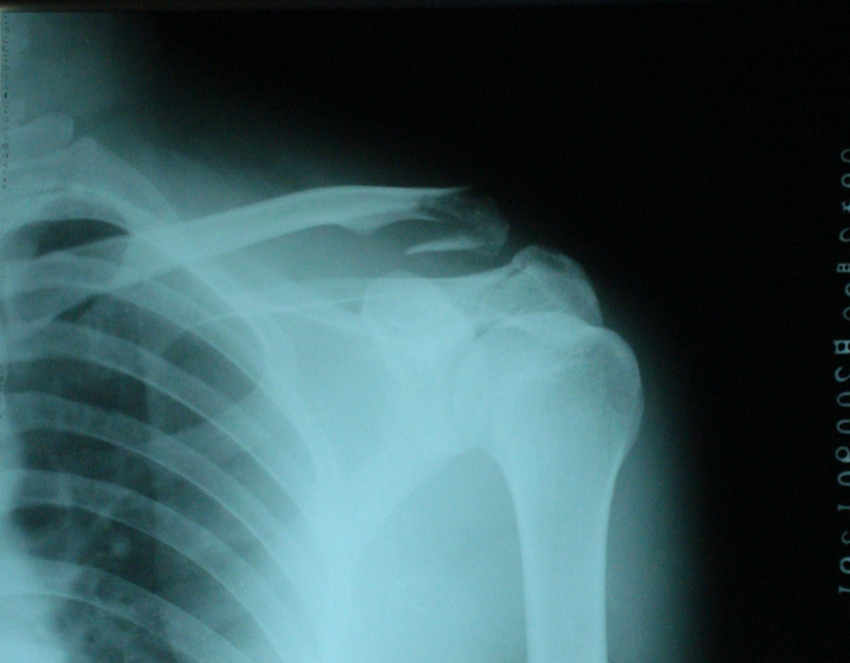

带线锚钉治疗锁骨远端不稳定骨折

锁骨远端骨折:锁骨远端骨折后常导致骨折不稳定,其引起不稳定的主要原因是骨折近端因失去了锁骨的完整性且喙锁韧带连接破坏而被斜方肌牵拉上移;远端骨折则靠喙锁韧带和关节囊完整与肩峰相连而保持原位。

对于锁骨远端不稳定性骨折过去先后采取了多种治疗方法:经肩峰穿克氏针固定、喙锁螺钉固定术、钩板内固定术及单纯缝线固定等等,但每一种固定方法都存在不同的缺陷。缝合锚钉的出现为锁骨远端不稳定性骨折的治疗提供了新方法。

Harrisbl比较了喙锁韧带修复加强的方法后发现在最大抗张强度方面,缝合锚钉尾线与正常喙锁韧带相似,符合肩锁关节的微动关节生物力学环境。其在喙锁韧带自然对合修复过程中能够维持足够强拉伸力,提供最佳软组织-骨之间连接。

锚钉的选择:SUPER带线缝合锚钉。